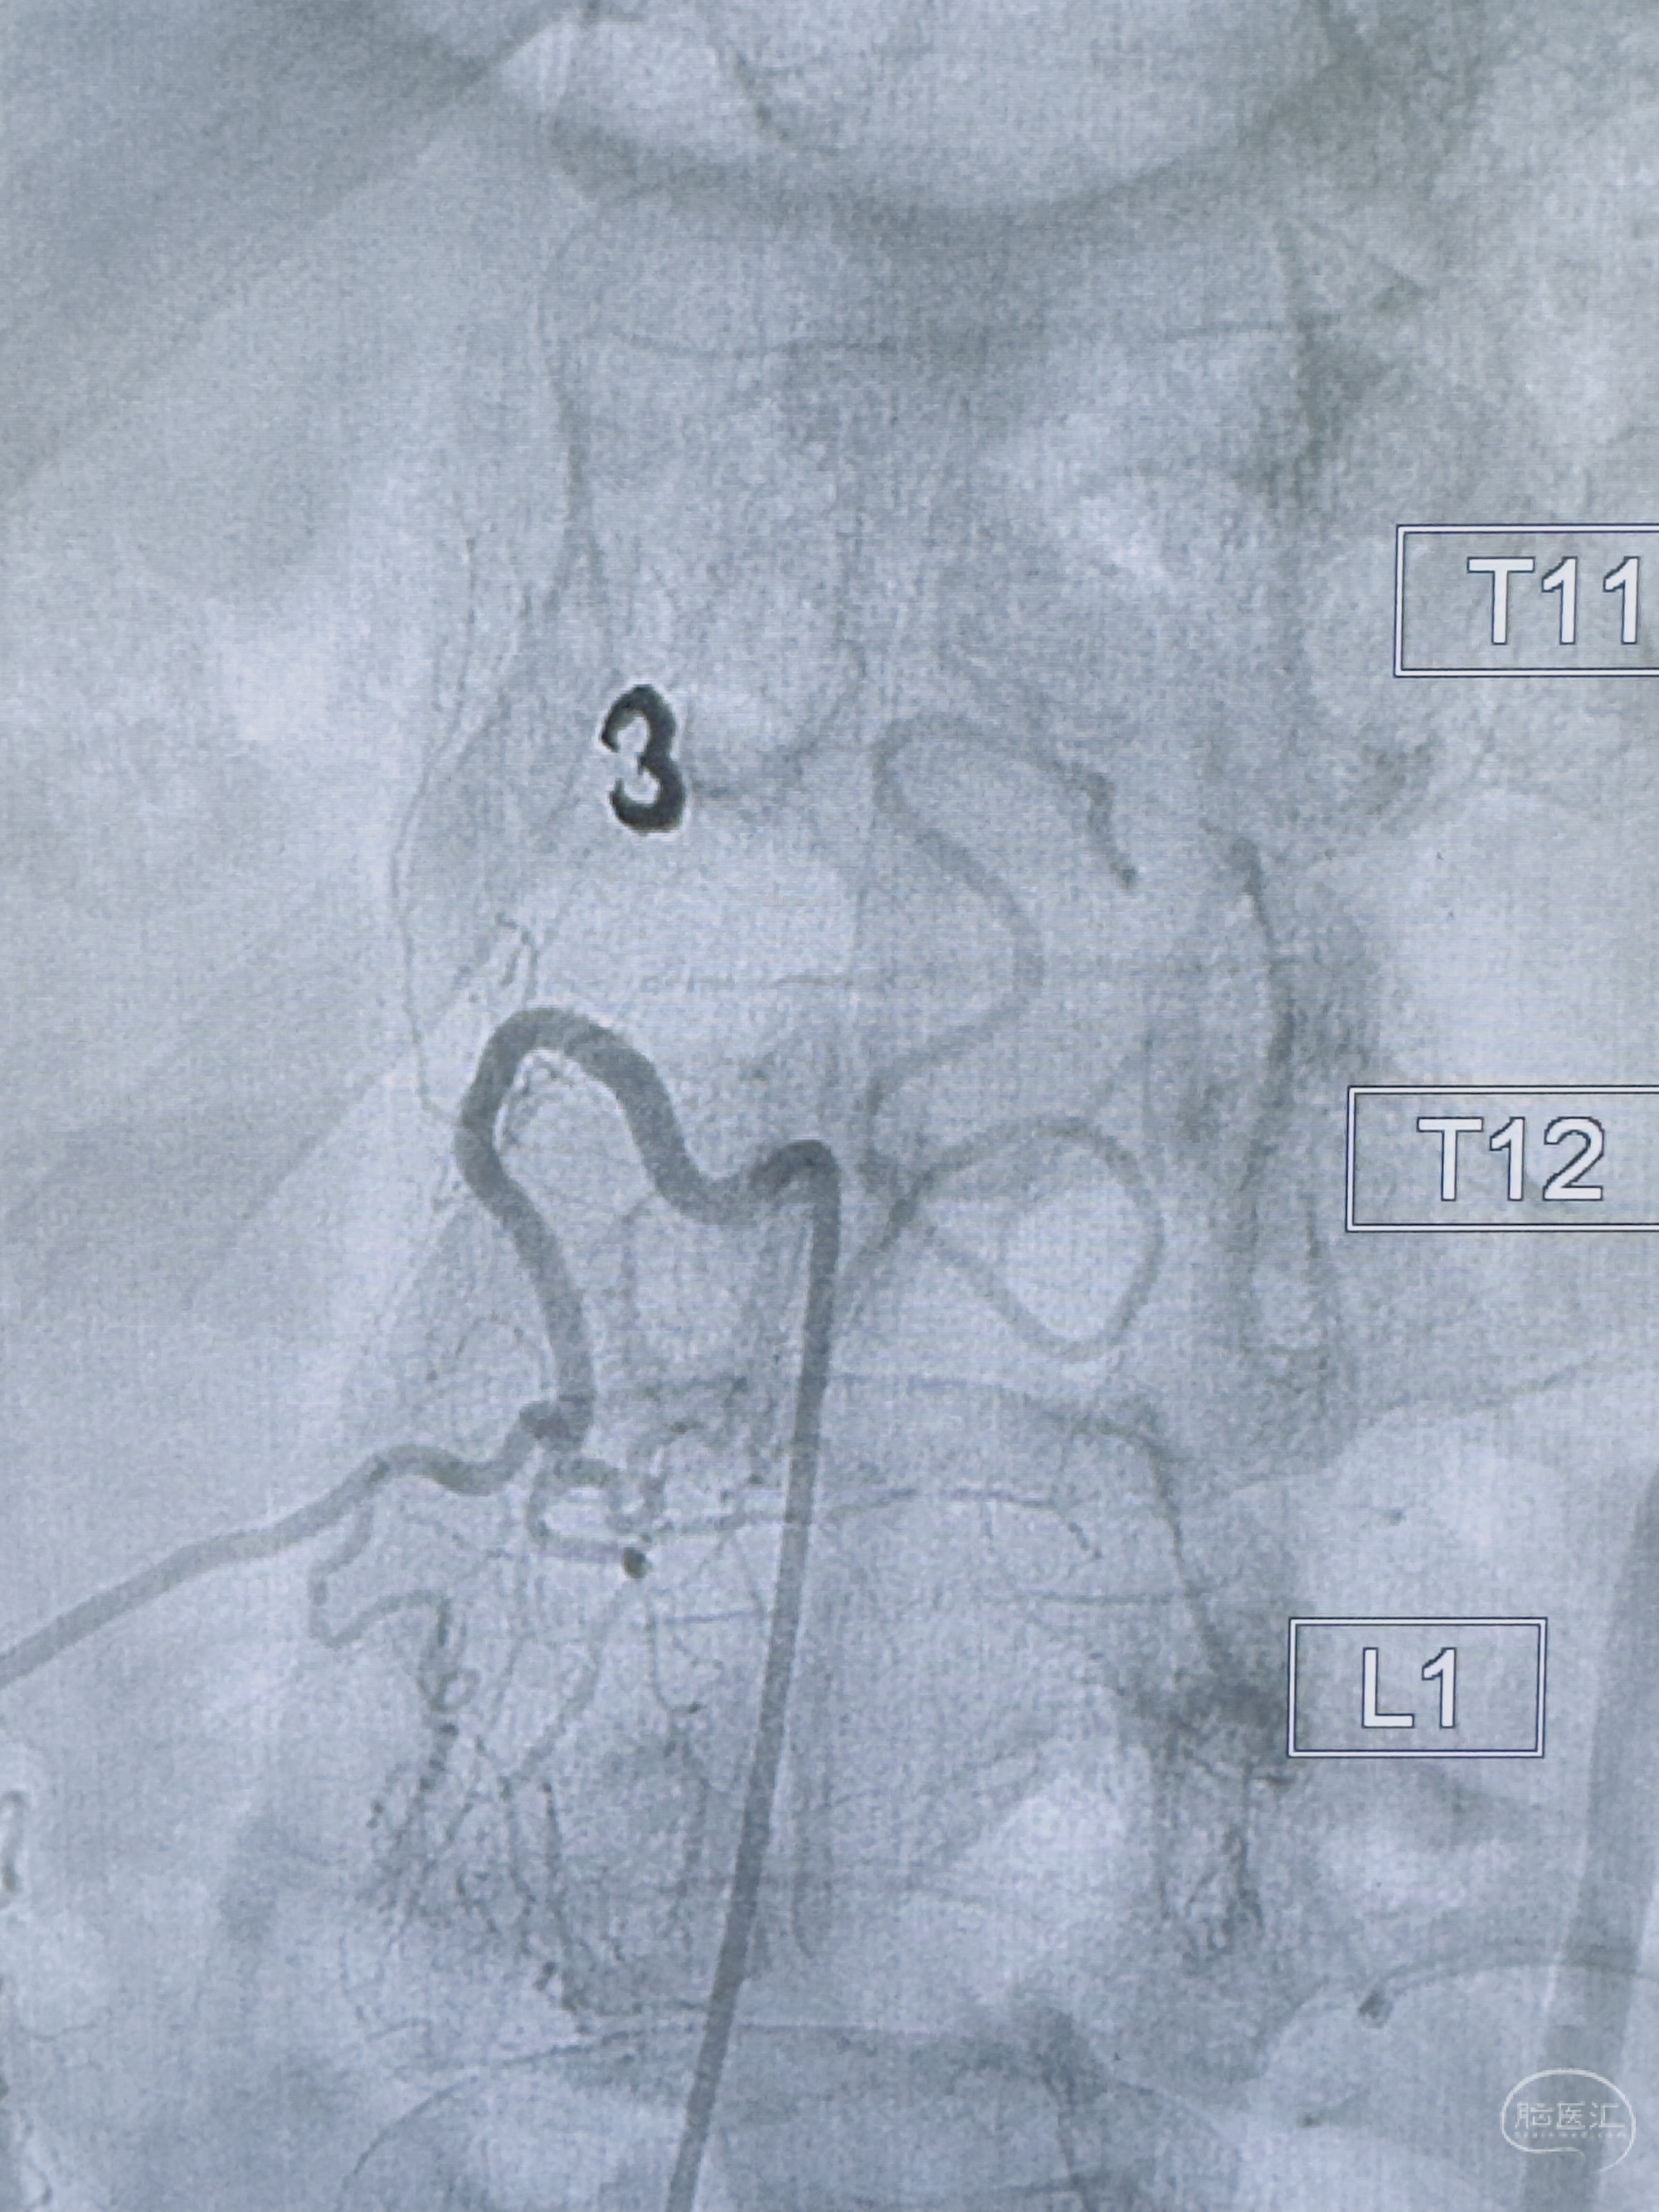

2023-10-13DSA:右侧L1水平硬脊膜动静脉瘘,供血动脉为右侧L1,附近动脉未见明确吻合供血,供血动脉处可见脊髓前动脉发出